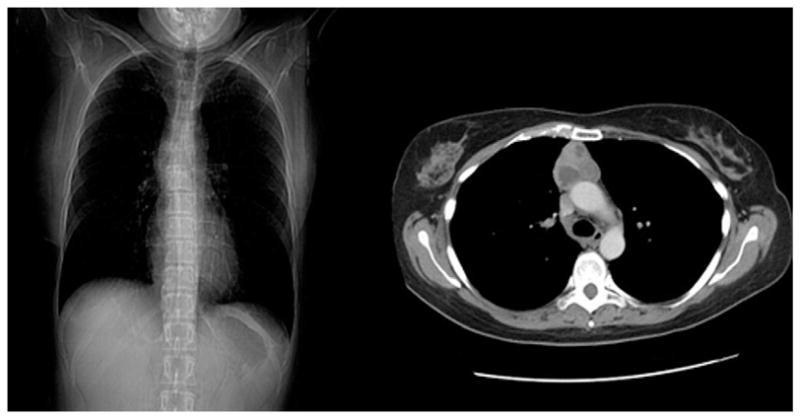

Gambar 1. Foto polos vs CT Scan pada pasien dengan Timoma